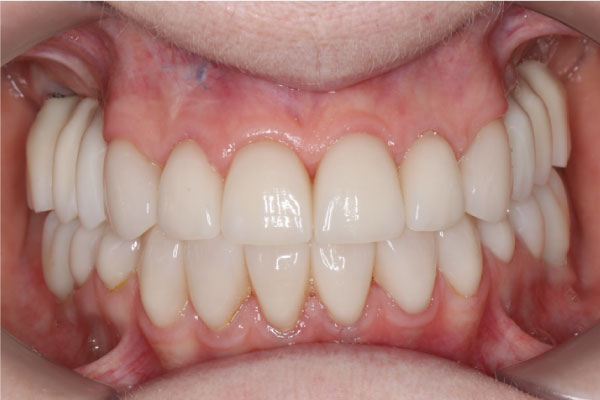

Имплантация зубов: фото "До" и "После"

Фото ДО

Фото ПОСЛЕ

Наведите для просмотра

All-on-4